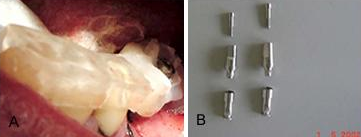

A primeira fotografia mostra uma fase muito importante, onde o guia cirúrgico é reposicionado na boca do paciente, com os desgastes necessários para ser fixados com acrílico aos mota implantes, que servirão se posicionadores para os similares que serão usados no modelo de trabalho. A foto 9B, mostra os componentes básicos que serão usados no laboratório, o similar e o conector onde a coroa será feita para ser parafusada no implante Conect.

A fotografia 10 A, mostra o momento em que o guia cirúrgico foi retirado da boca do paciente onde estão fixados os monta implantes para posicionamento no modelo. Na fotografia 10B, os similares estão já parafusados e o conjunto está pronto para ser fixado no modelo que servirá para o trabalho de confecção das coroas.